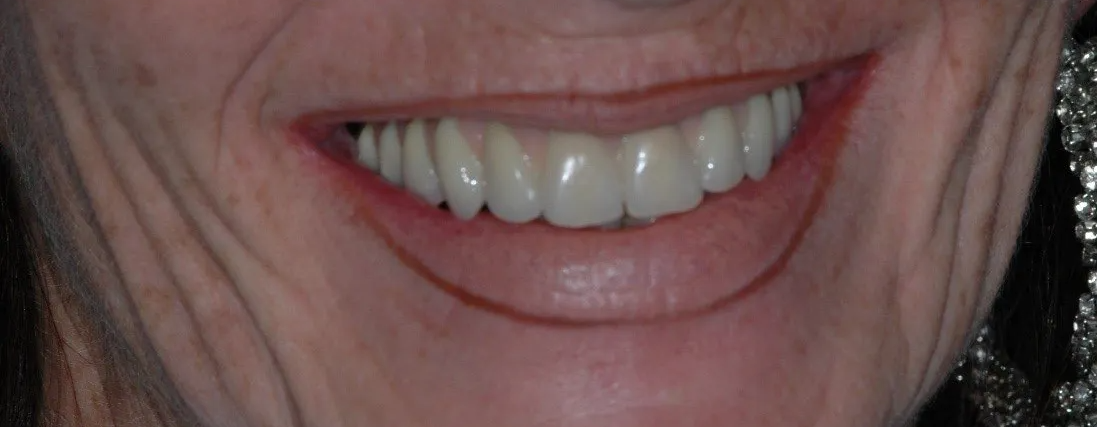

Il sorriso di un Toronto Bridge (6)